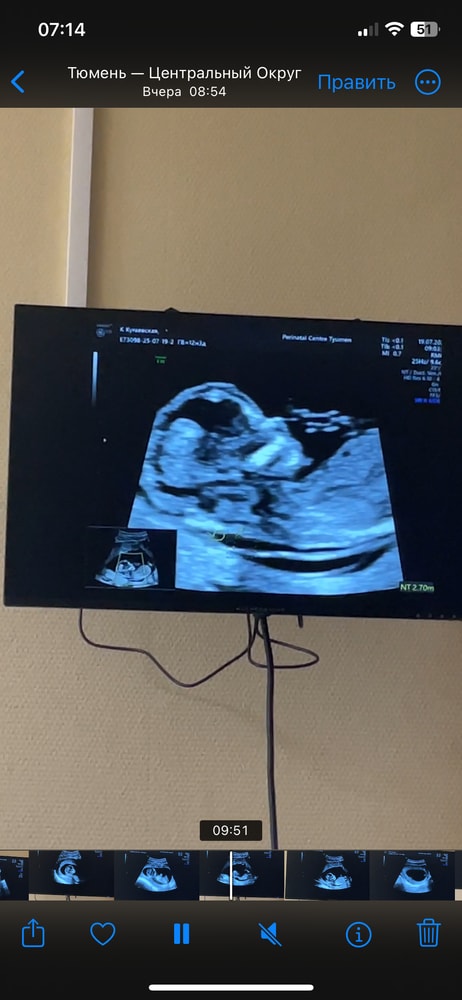

на 1 скрининге на сроке 12.4 недели

ктр 7,1см

Твп 2,8мм

срок по узи 13,2 недели.

все остальные показатели в норме. На узи напугали про твп чуть выше нормы.

Сильно страшно?